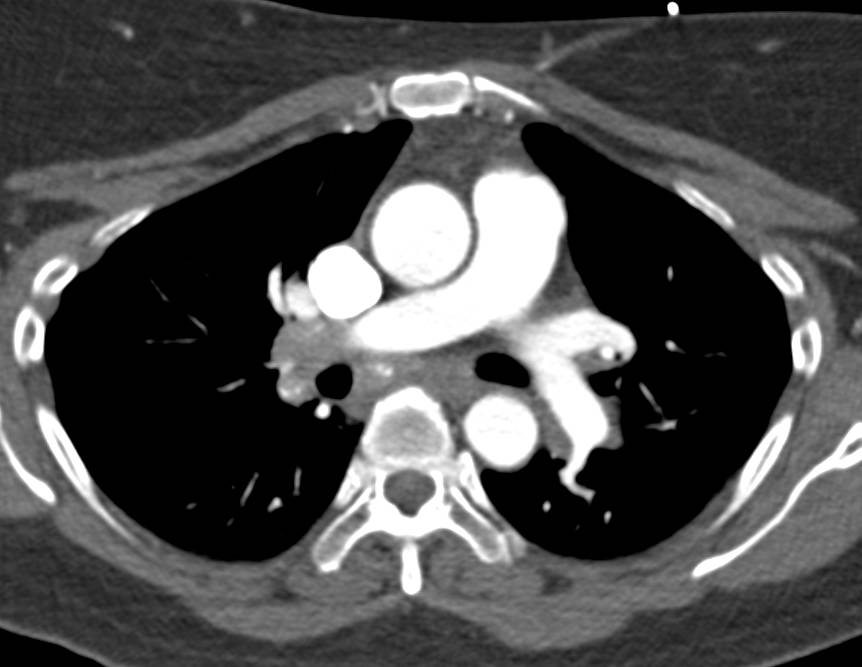

Septic Emboli in a Cancer Patient